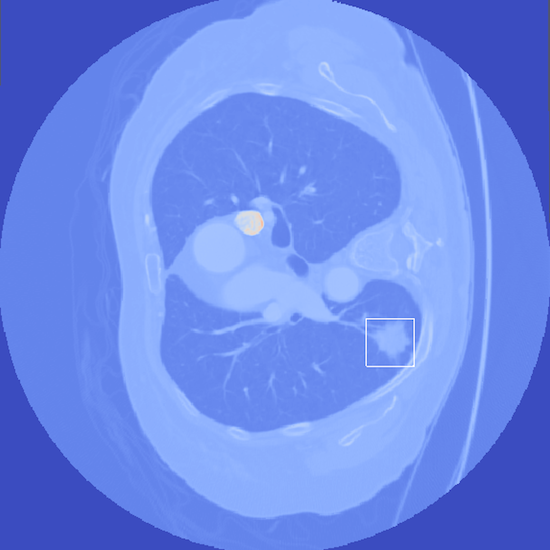

Improving Detection Rates of Lung Nodules Using Curvature Features

- Abstract: An exploration of whether conventional detection methods of lung cancers in low dose spiral CT scan could be improved using curvature features. In general, a large source of inaccuracy in detection rates can be attributed to irrelevant anatomical structures such as blood vessels. Often these irrelevant anatomical structures have different shape characteristics from lung nodules. For example lung nodules tend to appear bloblike as oppose to blood vessels, which appear cylindrical, or organ walls, which appear planelike. These curvature features were determined using eigenanalysis of the local second order image Hessian of each voxel, where the principal values are indicative of the local shape and provide more information than analysis performed on first derivatives alone.

- Method Overview: In each CT scan, the internal 3D lung volume was isolated using standard thresholding of pressurevalues ranges associated with lung parenchyma. The remaining voxels were conjoined using a connected components method, implemented through a union-find method, with small and isolated components removed. The remaining gaps were filled in using a standard 3D image closure method. First and second order partial derivatives were computed using Deriche filters, chosen for their stability and suitability in medical image scans. Then, for each of the voxels in the internal volume of the lung the local second order Image Hessian was generated and analyzed for preferred directions using eigenanalysis. This information was then used to weight the contribution of each voxel to standard lung nodule detection methods, to determine if giving stronger weight to voxels with local blob-like shape improved detections results.

Top row: An image slice demonstrating the lung Isolation process, enacted on a low dose spiral CT scan taken from the LIDC-IDRI database.

Bottom Row: Examples of lung nodule detections.